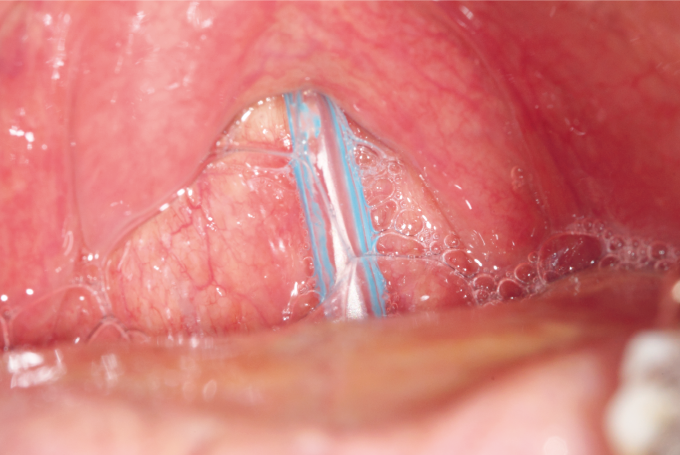

❷上咽頭後壁にチューブを挿入し、さらにチューブを進める(上咽頭通過)。チューブを1/3ぐらい挿入したところで、いったん挿入を止め、チューブを仮止めし、口腔内の観察を行う。

指ガードを装着して舌を押さえ、ペンライトで照らして(図8)、チューブが口腔内でとぐろを巻いていないこと、咽頭部を交差して走行していないことを確認する。

図8 指ガードを装着して舌を押さえペンライトで照らす

■チューブが、挿入した鼻孔と同側の梨状陥凹を通過せず、咽頭部を交差して走行していると、嚥下時に喉頭蓋の閉鎖を妨げる場合があり、誤嚥の誘因となる。